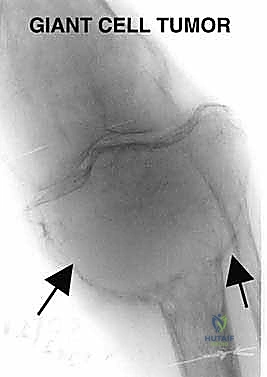

على الرغم من أنها تُصنف كأورام "حميدة" لأنها لا تنتشر (لا تعطي نقائل) إلى أعضاء أخرى مثل الرئتين، إلا أنها "عدوانية محلياً". هذا يعني أنها تنمو بشكل كبير وتدمر العظم المفصلي المحيط بها بالكامل، مما يجعل العظم هشاً وعرضة للكسر، ويدمر وظيفة المفصل.

* ورم الخلايا العملاقة (Giant Cell Tumor - GCT): هو المثال الأبرز في هذه الفئة. ينشأ غالباً في نهايات العظام الطويلة بالقرب من المفصل (مثل الظنبوب القريب). في الحالات المتقدمة التي يدمر فيها الورم القشرة العظمية وسطح المفصل، يصبح الاستئصال الكامل وإعادة البناء بالطرف الصناعي هو الخيار الأمثل لمنع عودة الورم (Recurrence).